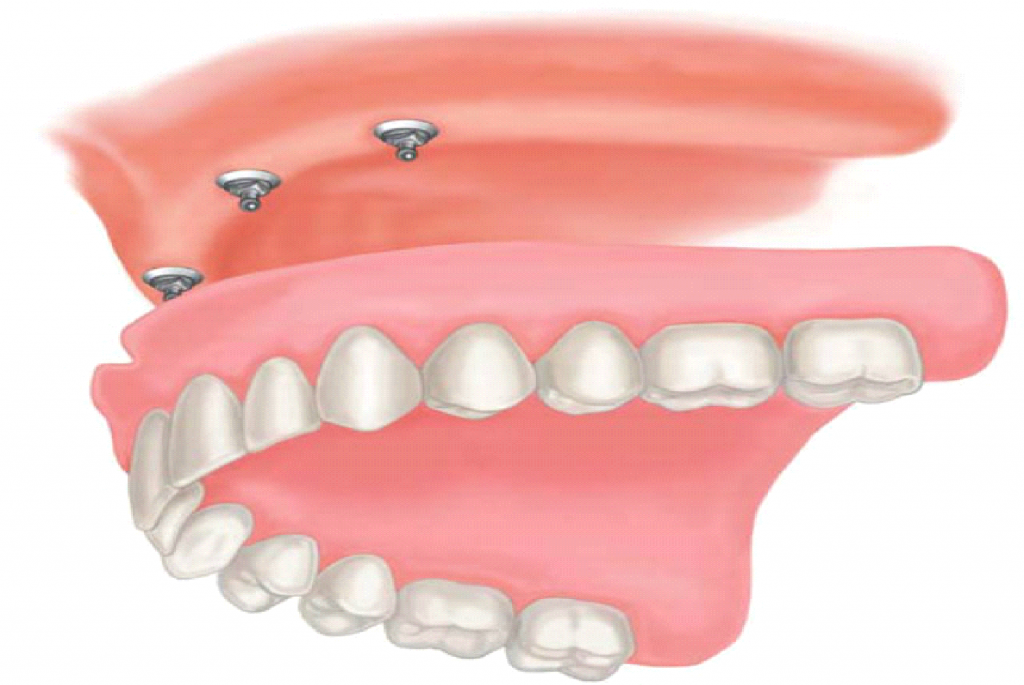

Современные съемные протезы на локаторах: Фото и примеры